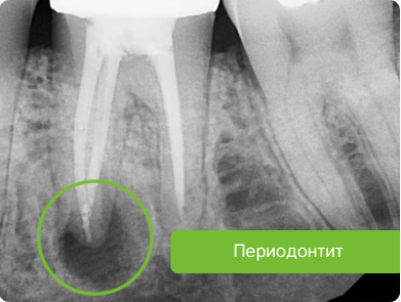

Апикальный периодонтит

Периапикальный или апикальный периодонтит – это воспаление тканей, окружающих верхушку корня зуба. Периапикальное воспаление часто является следствием инфицирования пульпы зуба, что, в свою очередь, чаще всего происходит по причине обширного кариозного поражения зуба. Периапикальное воспаление часто сопровождается резорбцией костной ткани и, иногда, верхушки корня зуба. Однако периапикальные ткани обладают способностью к заживлению, если устранить причину воспаления. Периапикальный периодонтит можно разделить на острый и хронический.

Хронический апикальный периодонтит - это слабовыраженная инфекция, возникающая, как правило, после острой инфекции, которая не была устранена полностью или лечилась неадекватно.

• образование периапикальной гранулемы;

• образование кисты в верхушке пораженного зуба (радикулярная киста);